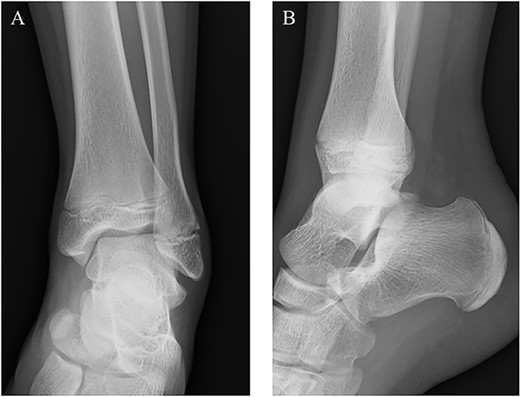

A 14-year-old male soccer player who belonged to a junior high school soccer club complained of right heel pain without trauma histories when he was playing a soccer. He had no medical history. He visited a local clinic and was treated with conservative treatment including rest, a non-weightbearing splint and anti-inflammatory medication for 4 days. However, his symptoms got worse, and so he visited our hospital. At the first visit to our hospital, physical examination revealed redness, local heat, swelling and tenderness around the insertion of the Achilles tendon. Also, his right foot was in equinus position, and it was difficult to correct his foot position accurate due to his heel pain (Fig. 1). Plain radiographs showed no abnormal findings (Fig. 2). Magnetic resonance imaging (MRI) demonstrated a low intensity signal on T1-weighted images and a high intensity signal on T2-weighted images in the retrocalcaneal bursa (Fig. 3). Laboratory examination revealed 2.1 mg/dL of C-reactive protein and 7.5 cells × 103/μL of white blood cell count. In addition, ultrasound-guided needle aspiration of the retrocalcaneal bursa resulted in 3 ml of purulent material and in which was positive for methicillin-susceptible Staphylococcus aureus (MSSA). We diagnosed him with septic RB caused by MSSA and started to treat with conservative treatment including a non-weightbearing splint and intravenous antibiotics therapy using cefazolin (6000 mg per day). However, his symptoms and laboratory results did not improve at 4 days after starting intravenous antibiotics therapy, and so we applied hindfoot endoscopic bursectomy for him.

Plain radiographs of the right ankle showed no abnormal findings in (A) anteroposterior and (B) lateral views.